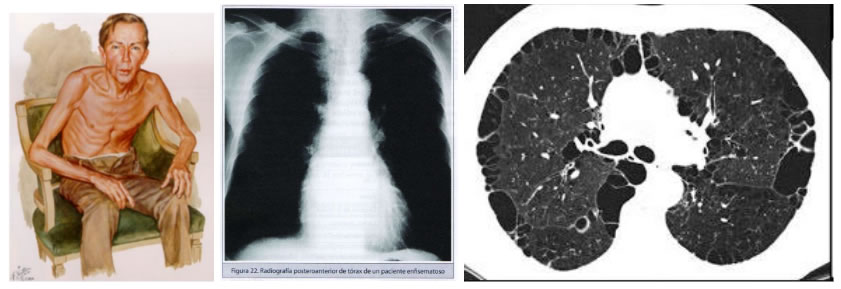

ENFISEMA PULMONAR: destrucción y dilatación de los espacios alveolares que alteran intercambio.

Figura 6. Pink buffer, actualización de la guía española para el manejo de la EPOC (GesEPOC2017)

Figura 7. Manual CTO Neumología y Cirugía Torácica, 8va edición.

Figura 8. Video aula radiología, radiology with Jezreel noviembre 2016.

- Enfisema: su primera manifestación disnea acompañado de tos seca con labio fruncido, a eso se debe el nombre de sopladores rosado, con pérdida de masa corporal, así como aumento de la dificultad respiratoria a mínimos esfuerzos.

- Enfisema pulmonar: disminución murmullo vesicular pulmonar generalizado, hiperresonancia e hipertransparencia en la radiografía con descenso del diafragma y presencia Bullas enfisematosas.